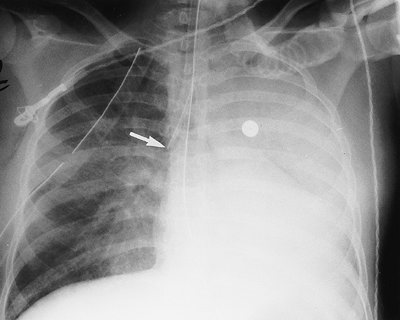

none should be present during diastole. If the catheter is short, dislodgment may occur, and the catheter may enter the right atrium, pulmonary artery, SVC, or coronary sinus. If the lead is too long, a bend in the wire may occur, causing lead fracture (Fig. 5-22). A redundant lead may also perforate the myocardium; this complication generally occurs at the time of or within a few days after insertion. The frontal or lateral radiograph will show the catheter tip outside or within 3 mm of the edge of the cardiac silhouette (Fig. 5-23). Perforation can lead to cardiac tamponade or postcardiotomy syndrome. Inflammation and infection can occur within the vein or the generator pocket; the latter occurs in up to 5% of patients (20). Major vein thrombosis and pulmonary embolism are additional complications of pacemaker insertion.

FIGURE 5-22. Looped pacer lead. PA (A) and lateral (B) chest radiographs show looping of the pacer lead over the area of the expected tricuspid valve (arrow). This positioning can result in dysrhythmia, lead fracture, or myocardial perforation.